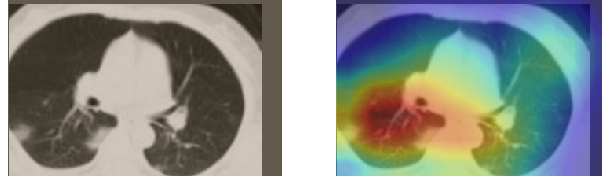

In order to make our models more transparent and provide detailed visual analysis, we present the Grad-CAM localization maps obtained by different models. We consider CT images with COVID-19 abnormalities from the test set of each dataset and highlight the important regions considered for the prediction. For the SARS-CoV-2 dataset we use the Inception V3 model. Figure 13 shows the original CT images and their localization maps. Our model is capable to detect regions that show abnormalities in the CT scans.

In a similar way, we consider classifying the test CT scans from the COVID-19 dataset by the DenseNet169 model and highlight the important regions considered for predictions. We present the original CT images and their localization maps in Figure 13. We can also see that our model is capable to detect the COVID-19 related regions as marked (small square in some images) by expert radiologists.

A wide variety of typical and atypical CT abnormalities have been reported for COVID-19 patients in various studies [58, 59]. So, we tested our models on external CT images extracted from these two publications as they feature typical findings of COVID-19 pneumonia marked by specialists. In order to make sure that not any of the extracted images are unintentionally included in our datasets, specifically the COVID19-CT dataset, we use the model trained on the SARS-CoV-2 dataset. First, the InceptionV3 model is employed to classify the extracted CT images. The model is able to correctly classify the given CT images as COVID-19. Second, in order to interpret the model’s generalization capabilities, we apply the Grad-CAM technique to visualize the regions of abnormalities that are considered. By assessing the different CT images in Figure 15, we can see that the model accurately localizes the disease-related regions. Even more interesting is the fact that the model ignores any specific marks in the images like letters and only localizes the COVID-19 related regions. These visual explanations show the success of our models to learn relevant, generic visual features related to COVID-19 and are capable to correctly classify CT images outside the datasets on which they are trained.

Figure 16 shows various CT scans where only one lung is visible. The CT scans are also extracted from the paper [58] and show different CT manifestations of COVID-19 pneumonia marked by red squares. The InceptionV3 model is capable to classify them correctly as COVID-19, although it is trained on CT scans where the entire lung is visible. Intriguingly, when applying Grad-CAM we can see that all regions of abnormalities are accurately localized. This also proves the potential of our model to detect COVID-19 abnormalities in CT images outside the dataset used for training.